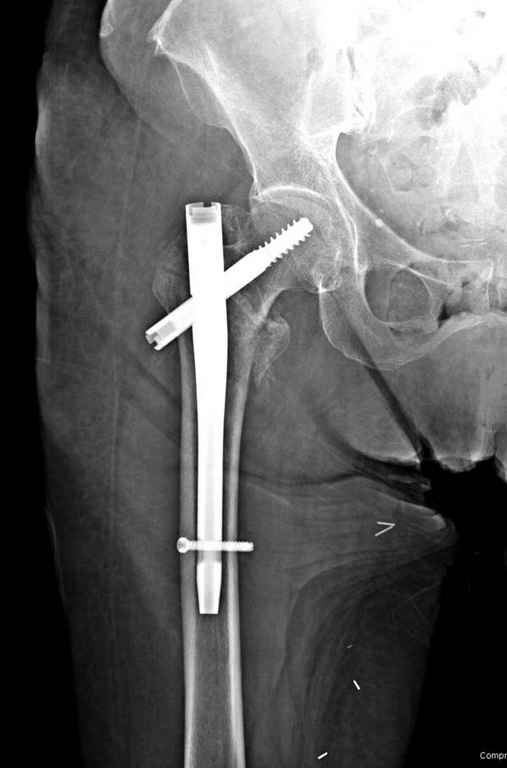

С приходом менее агрессивных блокируемых цефаломедуллярных гвоздей (Gamma 3 и другие) изменилась тактика лечения. Несмотря на то, что вся стабильность держится вокруг одного блокирующего винта, в большинстве случаев гвозди приводили к успеху.

Вашему вниманию представляется похожий случай, пациентке 70, осложнился в течение одного месяца после операции. Ревизия с заменой сустава, кабельная фиксация на трохантер. При установке в дистальном диафизе обнаружен тонкий кортикальный слой и сделана профилактика от возможного перелома аллографтом.